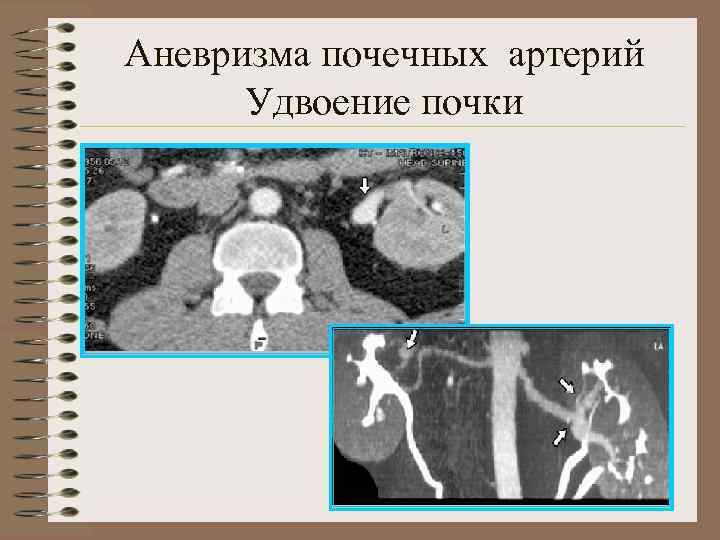

Аномалии почечных артерий 1. Аномалии положения и количества почечных артерий • Агенезия почечной артерии • Гипоплазия почечной артерии • Добавочная почечная артерия • Двойная почечная артерия • Множественные артерии 2. Аномалии формы и структуры артериальных стволов • А. аневризма почечных артерий • Б. фибромускулярный стеноз • В. Артерио-венозные фистулы

Аневризма почечных артерий Удвоение почки